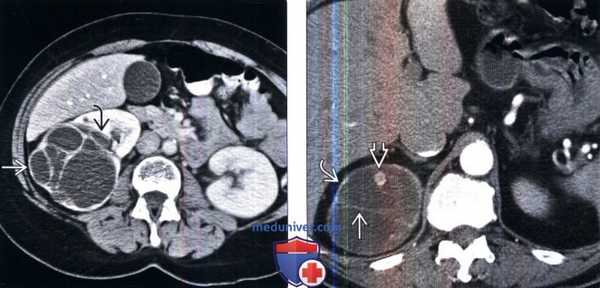

(Слева) КТ с контрастированием, аксиальная проекция: многокамерное кистозное образование с перегородкой и измеряемым контрастированием (класс 3 по Босняку). Имеется инвагинация образования в почечный синус, что служит характерным признаком многокамерной кистозной нефромы.

(Справа) КТ с контрастированием, аксиальная проекция: кистозное образование верхнего полюса правой почки с тонкими перегородками, контра-стируемыми пристеночными узлами и тонкой стенкой. Данные признаки характерны для кисты класса 4 по Босняку. Она представляет собой случай кистозного ПКР Наличие контрастируемых узлов служит признаком злокачественности.